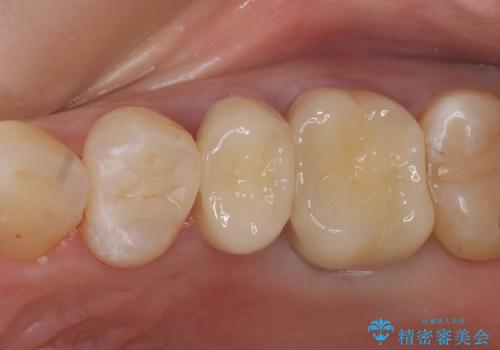

- 左上4、5、6番目の歯を白くしたいといらっしゃった方の症例です。

4番目の歯はセラミックインレーによる修復、5・6番目の歯はオールセラミッククラウンによる補綴を行いました。

今回用いたオールセラミッククラウンはジルコニアフレームという白い素材の上にセラミックを盛っているため、審美性が非常に高いのが特徴です。

また、ジルコニアは人工ダイヤモンドの材料にも使われているほど高い強度を持っており、そのためオールセラミッククラウンは審美性だけでなく、奥歯やブリッジの補綴も可能とするクラウンです。

当院のセラミックインレーはemaxという強度と審美性に優れた材料を使用しています。

またプレス方式でインレーを製作しているため、削り出しで製作するCADCAMより優れた適合性も持ち合わせており、虫歯が再発しにくい修復物です。